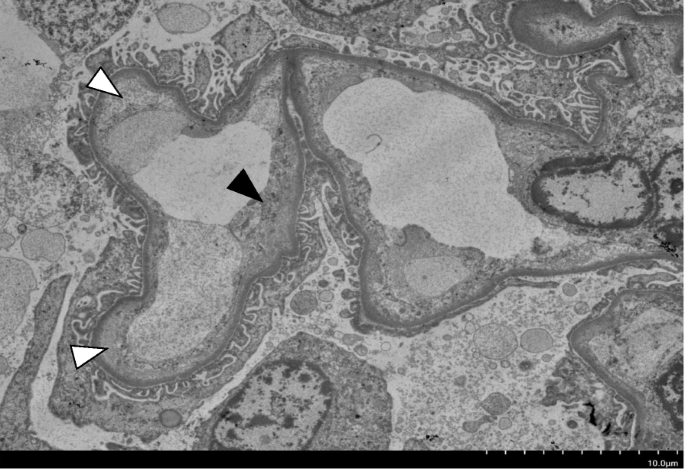

Autopsy, performed 3 h after death, revealed patho-anatomical diagnosis of lung congestions, with multiple carcinomas in the lungs, liver, adrenal glands, and thoracic spine. Regarding kidney tissues, the glomeruli were slightly enlarged, but with no thickening, doubling, or deposition of the basement membrane, and no significant finding on immunofluorescence study. Although edema was observed in the kidney interstitium, cell infiltration was mild, with no evidence of interstitial nephritis. Mild atherosclerotic lesions were found at the level of the arcuate to interlobular arteries, but with no thrombus formation. Wall edema and swelling with narrowing of the lumen were observed in arterioles, suggesting TMA (Fig. 2). Electron microscopical examination revealed subendothelial expansion and endothelial swelling of the glomeruli, consistent with the pathological feature of TMA (Fig. 3).

We identified one reported case of ICI-induced TMA and four reported cases of ICI-induced TTP (Table 2) [3, 12,13,14,15]. As the causative agents, three were nivolumab and four were ipilimumab, and two cases were combinations of these two drugs. To our knowledge, TMA possibly associated with pembrolizumab has not been reported so far. The time from the last administration of ICI to the onset of TMA/TTP was between 7 and 22 days in these cases including ours. In all cases, TMA/TTP continued even after drug discontinuation. This is probably due to residual activation of T cells by ICI and might be a characteristic finding of ICI-related TMA. Two patients had renal impairment, one of whom was able to withdraw from dialysis but the other was dependent on dialysis. The pathologic features characterizing chemotherapy-induced TMA are vascular damage manifested by arteriolar and glomerular capillary thrombosis with abnormalities in the endothelium and vessel wall, including thickened capillary walls, occlusion of vascular lumens, fibrin deposition, and endothelial separation, with expansion of the subendothelial zone [10]. Cancer drug-induced TMA is divided into two distinct categories: types I and II [10]. Type I cancer drug-induced TMA onsets usually 6–12 months after starting therapy in a dose-related manner. This type appears to have permanent and irreversible hematologic manifestations or kidney injury. Drug characteristic of type I include mitomycin C, gemcitabine, or platinum salts. The pathological finding is both arteriolar and glomerular capillary thrombosis in this type. On the contrary, type II cancer drug-induced TMA occurs any time after initiation of the treatment in a dose-unrelated manner. And this type has a high likelihood of recovery by stopping the drug. Drug characteristic of type II include VEGF pathway inhibitors. Glomerular capillary thrombosis lesions are exclusively found, but no arteriolar lesion in type II. We think our case was similar to type I rather than type II because irreversible thrombocytopenia and acute kidney injury persisted even after drug discontinuation and was associated with not only glomeruli but also arteriole lesions.